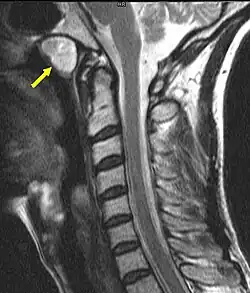

Eine Tornwaldt-Zyste (lateinisch Bursa pharyngea(lis)), (gelegentlich auch in den Schreibweisen Thornwaldt- oder Thornwald-Zyste) ist eine benigne Zyste (eine gutartige, flüssigkeitsgefüllte Raumforderung), die im oberen hinteren Nasopharynx (Nasen-Rachenraum) lokalisiert ist.

Sie wird meist zufällig bei der Computertomografie (CT) oder Magnetresonanztomografie (MRT) des Kopfes als in der Mittellinie gelegene, gut abgegrenzte rundliche Raumforderung diagnostiziert.[1]